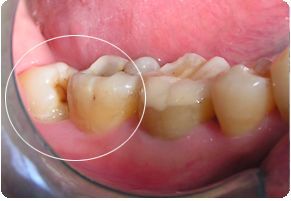

第二位患者同样姓张,但他在25岁的年纪,却已经被智齿疼痛折磨了2年多了。小张自述,自己的智齿疼,并不是“疼起来要人命”的那种,所以才一拖再拖。但近期,小张的下颌右侧牙龈反复长脓包,因担心病变扩大,才终于鼓足勇气走进了口腔科。医师在检查小张口内情况时看到,该患者下颌右侧第二磨牙牙冠表面完整,但在颊侧牙龈位置处,可见约5mm直径的脓包,脓包下,一颗牙冠倾斜部分微微露出的智齿隐约可见,而这两颗牙齿之间,竟有着大量嵌塞的食物,已然形成龋洞!并且第二磨牙周围骨质被破坏严重,牙齿已经是“悬浮”在牙槽窝内,这颗看似完整的牙齿因为智齿给予的阻力和龋洞的存在,其实已经不具有保留价值了,只能和智齿一起被连根拔除。